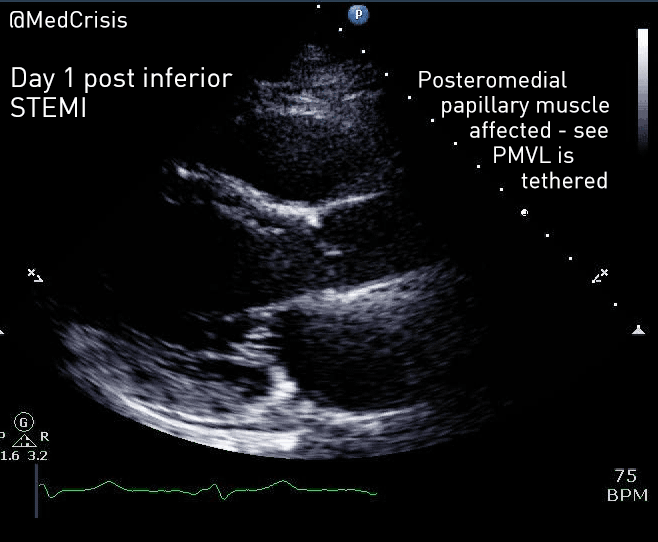

A bedside echocardiogram was performed.

A parasternal long axis view reveals the posterior mitral valve leaflet is tethered. The basal posterolateral wall is hypokinetic.

Therefore one can appreciate why mitral valve problems are more common following an inferior STEMI. In this case an almost akinetic segment, which included the posteromedial papillary muscle, caused the posterior mitral valve leaflet to become fixed, causing mitral regurgitation. Even though overall left ventricular function was only mildly impaired on the echocardiogram, the regurgitant pressure into the lungs can precipitate pulmonary oedema.